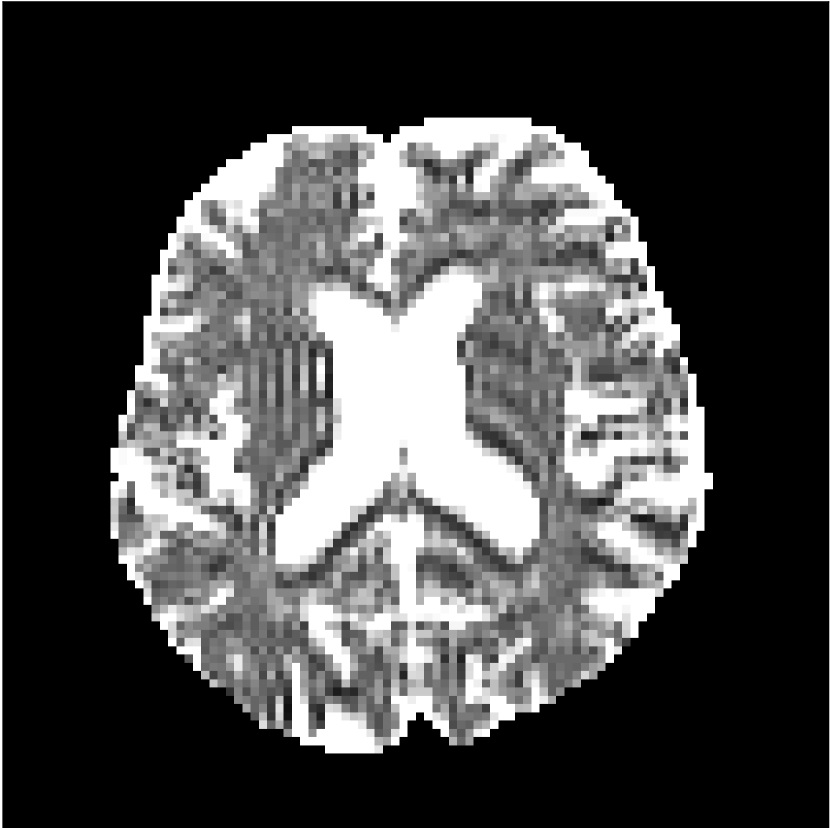

Figure 8 shows examples of non-diffusion-weighted images before and after processing. The raw images (Raw) served as the input for the magnitude deep learning (MCNN) and complex deep learning (CCNN) methods.

Raw 𝐱tsubscript𝐱𝑡\mathbf{x}_{t}

MCNN, fθ^(𝐱t)subscript𝑓^𝜃subscript𝐱𝑡f_{\hat{\theta}}\left(\mathbf{x}_{t}\right)

MCNN Resid., Ric(𝐱t)fθ^(𝐱t)Ricsubscript𝐱𝑡subscript𝑓^𝜃subscript𝐱𝑡\text{Ric}(\mathbf{x}_{t})-f_{\hat{\theta}}\left(\mathbf{x}_{t}\right)

CCNN, fθ^(𝐱t)subscript𝑓^𝜃subscript𝐱𝑡f_{\hat{\theta}}\left(\mathbf{x}_{t}\right)

CCNN Resid., Ric(𝐱t)fθ^(𝐱t)Ricsubscript𝐱𝑡subscript𝑓^𝜃subscript𝐱𝑡\text{Ric}(\mathbf{x}_{t})-f_{\hat{\theta}}\left(\mathbf{x}_{t}\right)

No PF

5/8 PF

Figure 8: Examples of non-diffusion-weighted images from in vivo data at b=0𝑏0b=0 s/mm2. Artifacts in the Raw image, 𝐱tsubscript𝐱𝑡\mathbf{x}_{t}, are corrected by the MCNN and CCNN models, fθ^(𝐱t)subscript𝑓^𝜃subscript𝐱𝑡f_{\hat{\theta}}(\mathbf{x}_{t}). Also shown are the residuals between the CNN corrections and the original Raw image with Rician bias correction Ric(𝐱t)Ricsubscript𝐱𝑡\text{Ric}(\mathbf{x}_{t}) [10]. The Gibbs artifacts removed by the methods are observed in the residuals. The MCNN method introduces some banding artifacts at the PF 5/8ths factor that are not present in the CCNN method.

Both methods remove artifacts, but the MCNN method allows residual rippling artifacts to pass through in the presence of partial Fourier. These rippling artifacts are not present in the CCNN method.